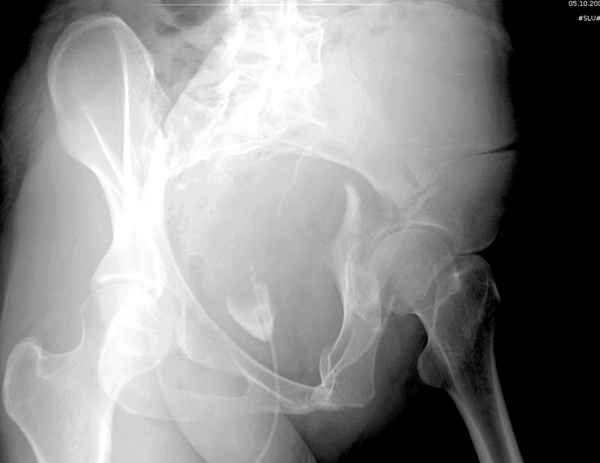

Из того минимума, что представлено, мне кажется, мы имеем дело с двухколонным переломом вертлужной впадины. Обычно медиальный (центральный) "вывих" головки встречаются в сложных двухколонных переломах со смещением.

По-моему, надо готовить больного к будущей артропластике, но без опоры на задний столб невозможно удержать протез. Опорная конструкция (кольца и т.д.) должны иметь опору, и поэтому мы бы сделали реостеосинтез задним доступом. При надобности остеотомия и рутинная фиксация с межколонными винтами.

В дальнейшем, время покажет, когда приступить к артропластике....

Здесь несколько вариантов двухколонных свежих переломов, которые были оперированы из одного-заднего, а также из двух: переднего и заднего доступов.